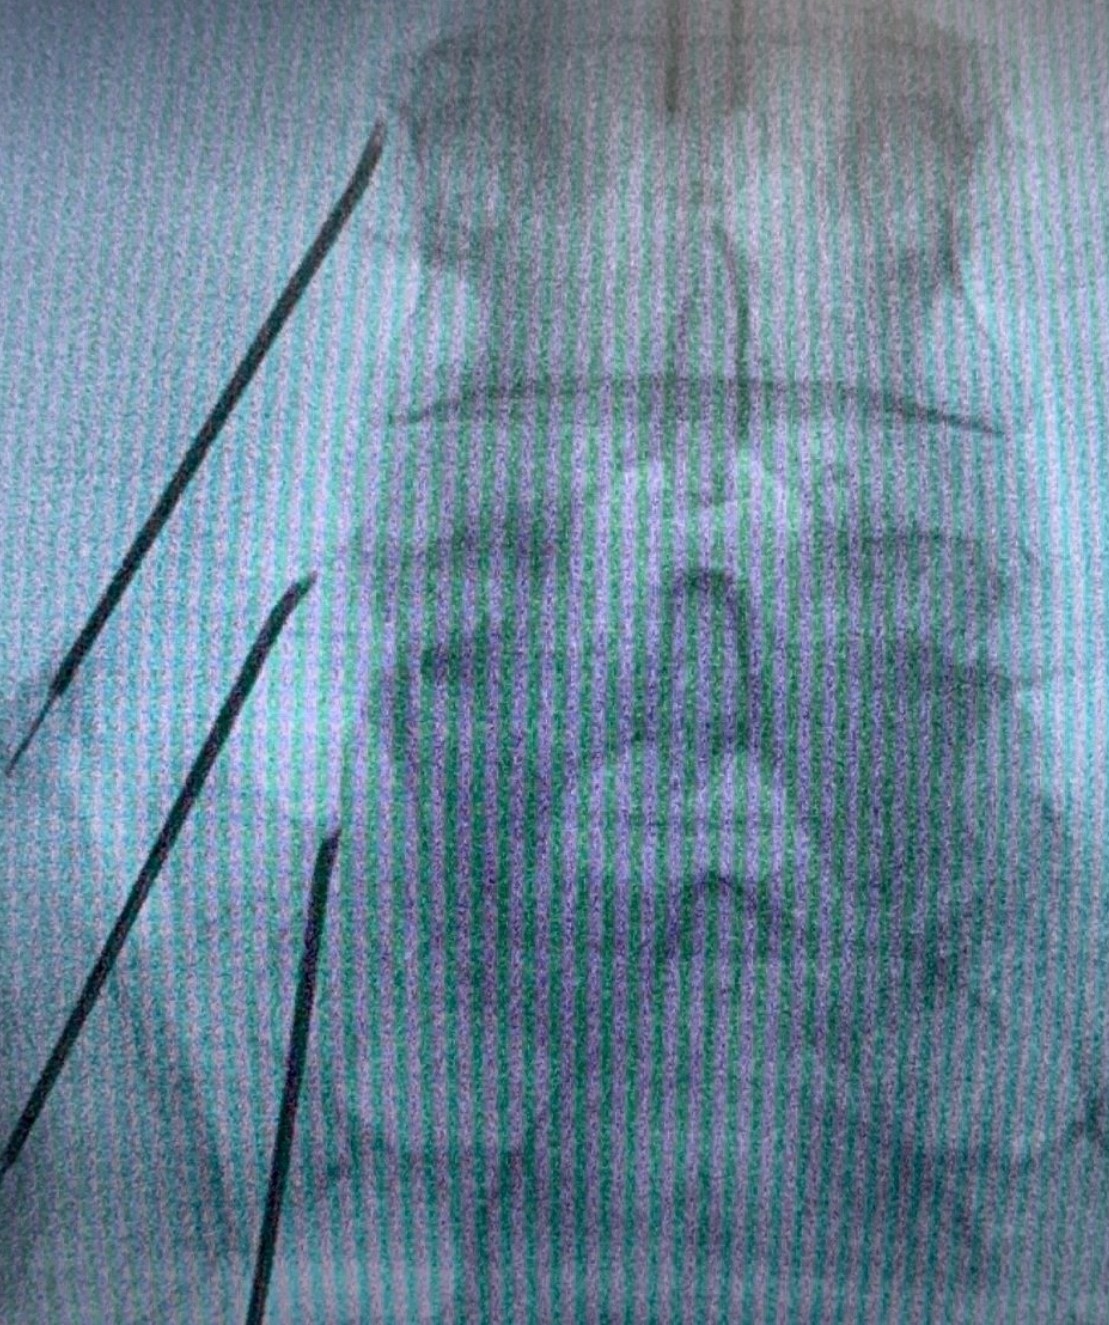

Τι είναι η νευρόλυση (RF-Ablation) των αρθρώσεων με χρήση ραδιοσυχνοτήτων

Πρόκειται για μια ελάχιστα επεμβατική τεχνική απονεύρωσης των αρθρώσεων της σπονδυλικής στήλης. Μπορεί να εφαρμοσθεί κατά τον ίδιο τρόπο στον αυχένα, στη ράχη και στην μέση. Στόχος της είναι η μακροπρόθεσμη ανακούφιση από τον πόνο των αρθρώσεων της σπονδυλικής στήλης, μέσω κατάλυσης των μέσων νευρικών κλάδων με χρήση της ενέργειας των ραδιοσυχνοτήτων. Προσφέρει ανακούφιση από τον πόνο για 9-15 μήνες συνήθως. Οι απολήξεις των νεύρων τείνουν να αναπλάθονται και ο πόνος μπορεί να επιστρέψει. Η διαδικασία μπορεί να επαναληφθεί χωρίς κανένα πρόβλημα εάν χρειασθεί.

Τι συμβαίνει κατά τη διάρκεια της νευρόλυσης

Χορηγείται τοπική αναισθησία για να μουδιάσει το δέρμα. Ο ιατρός κάτω από ακτινοσκοπική καθοδήγηση, εισάγει μια λεπτή ειδική βελόνα που στοχεύει το σημείο διέλευσης του μέσου νευρικού κλάδου, το οποίο βρίσκεται στη συμβολή της άνω αρθρικής και της εγκάρσιας απόφυσης του σπονδύλου στην οσφυϊκή μοίρα.

Στην πορεία ακολουθεί κινητικός και αισθητικός ερεθισμός του νεύρου. Αυτό μπορεί να οδηγήσει σε μικρούς τοπικούς μυϊκούς σπασμούς και να προκαλέσει λίγο πόνο. Μόλις ελεγχθεί η σωστή τοποθέτηση της βελόνας, χορηγείται τοπικό αναισθητικό και ακολουθεί η θερμοκαυτηρίαση του νεύρου.